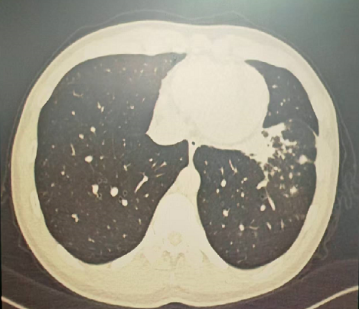

4月后再次复查胸部CT,提示病灶已经完全吸收。

明确诊断后我们给予了正规治疗,患者咳嗽症状迅速缓解,1月后复查胸部CT提示肺部病变大部分吸收。

以上是他的胸部CT影像,主要表现为左下肺炎症,片絮影+磨玻璃影。